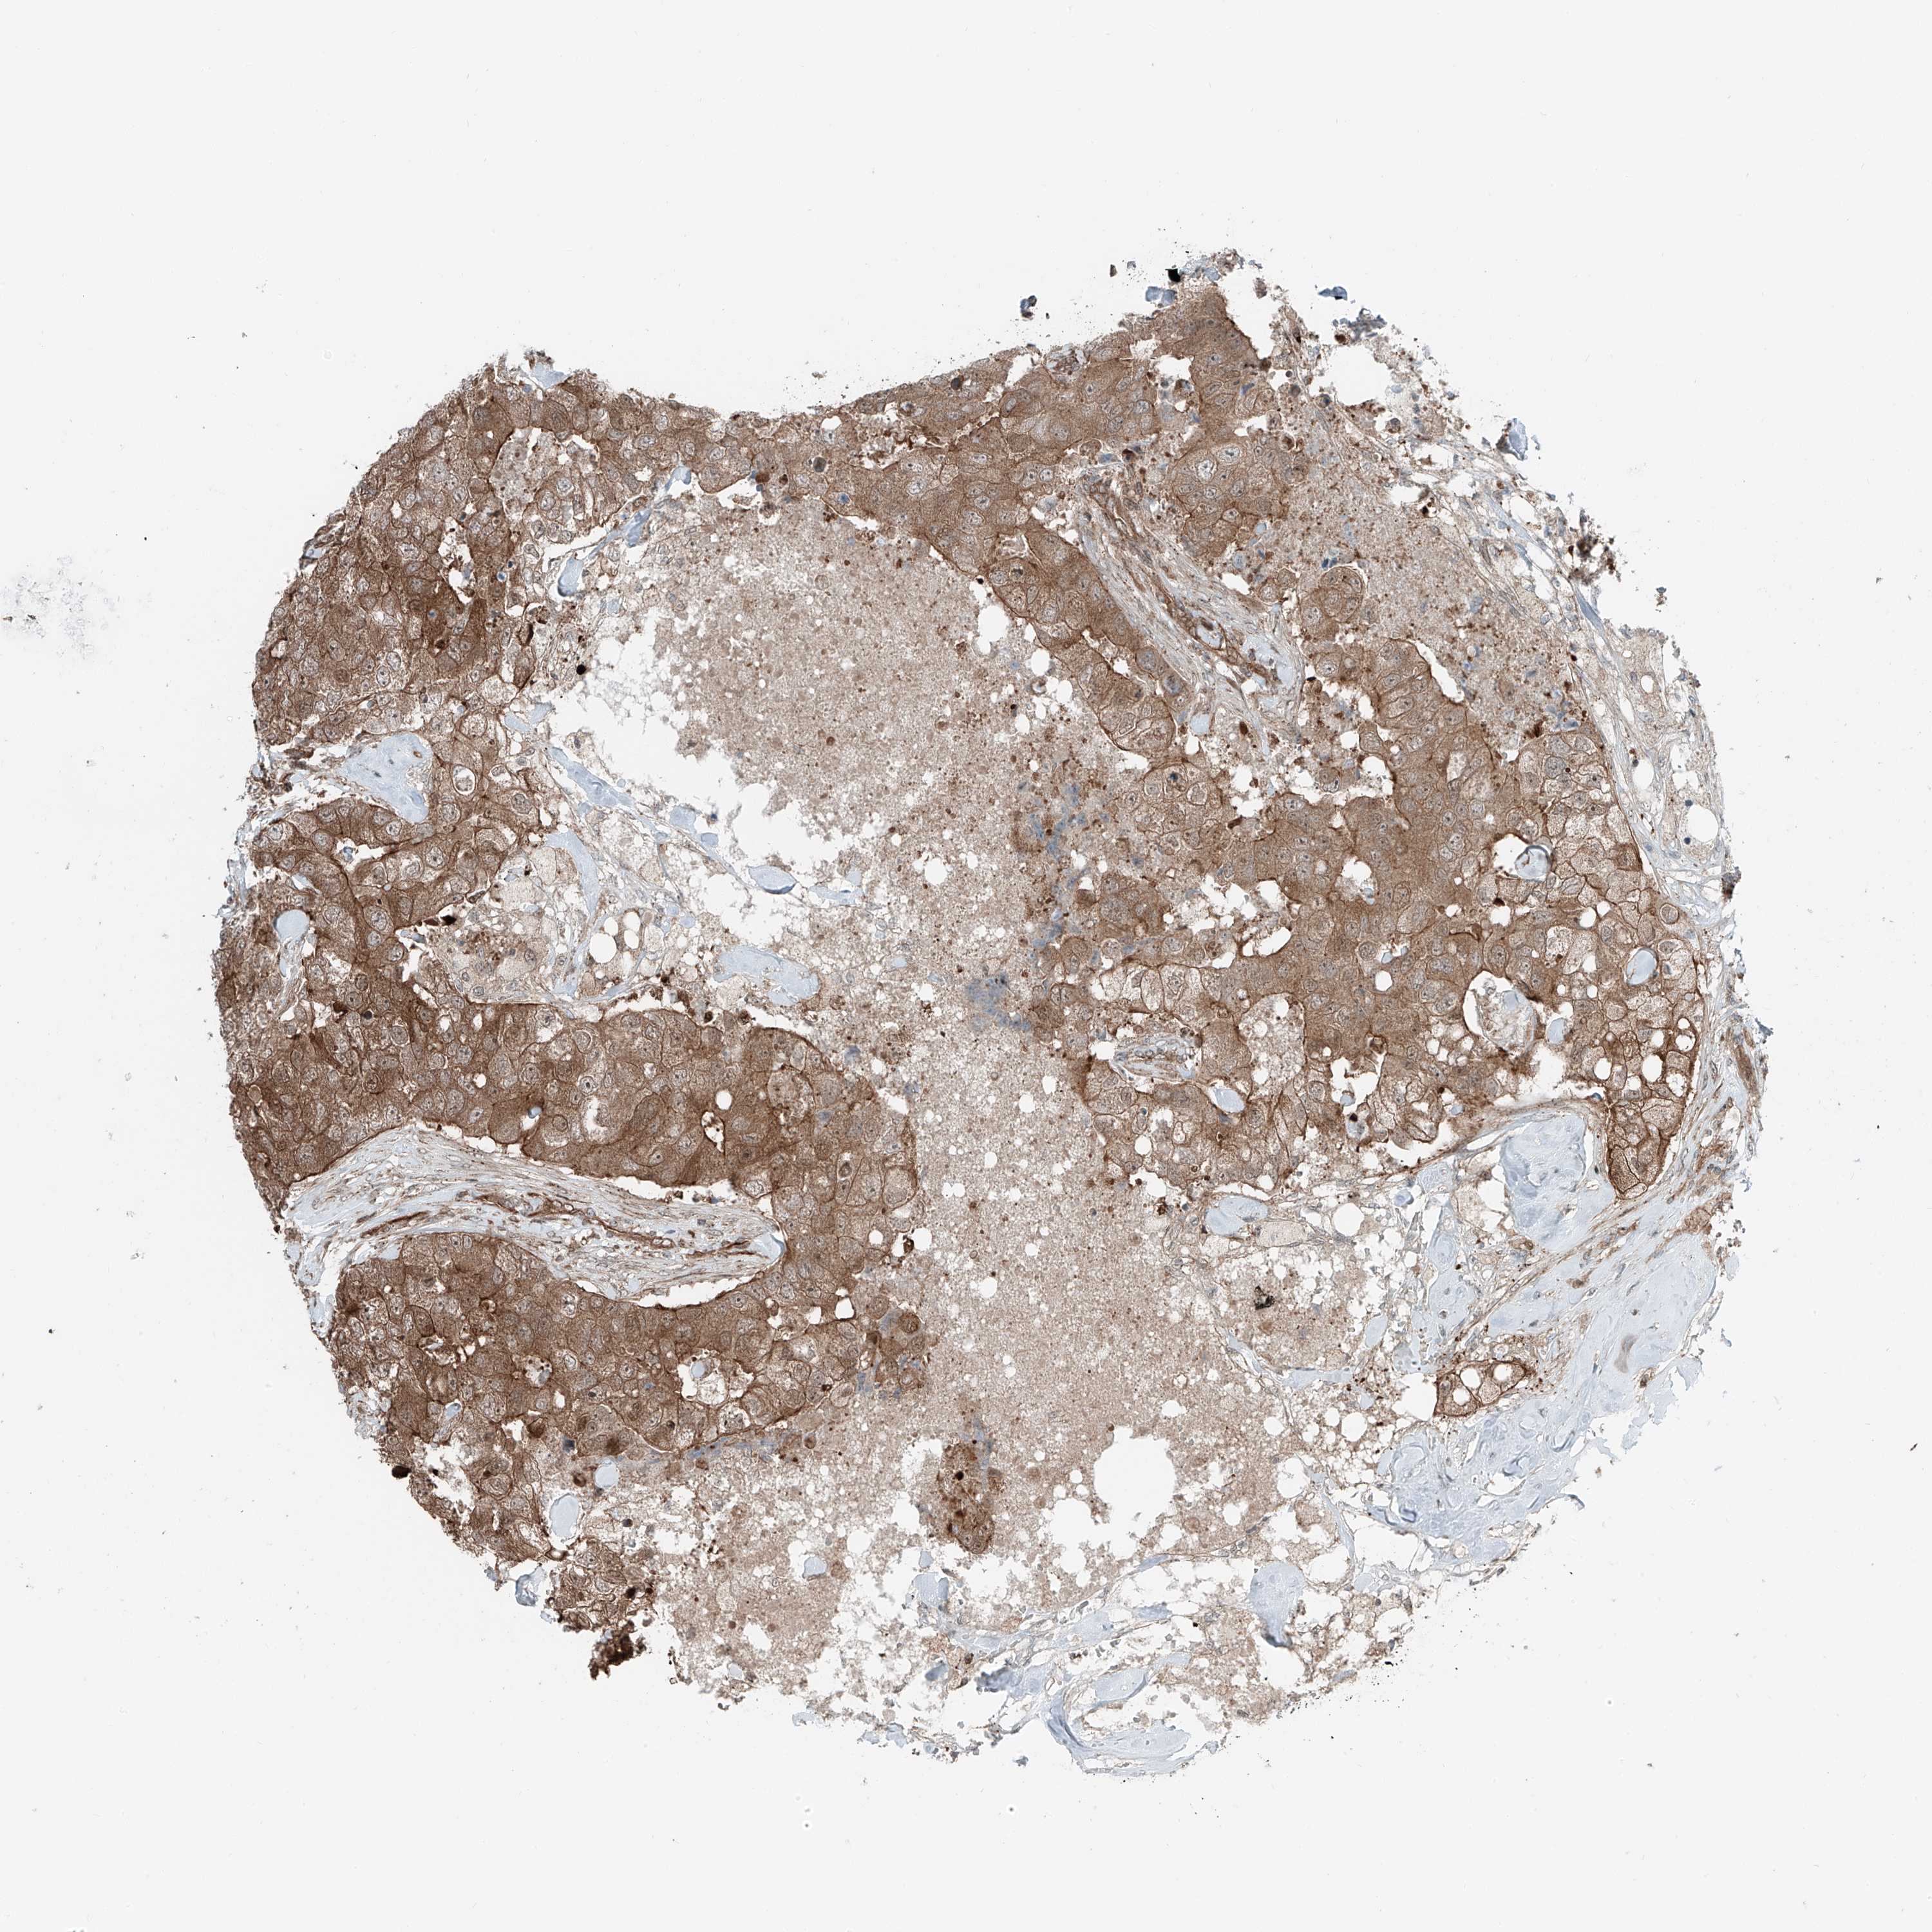

CANCER BREAST CANCER Show tissue menu

BRCA TCGA BRCA VALIDATION PROTEIN EXPRESSION